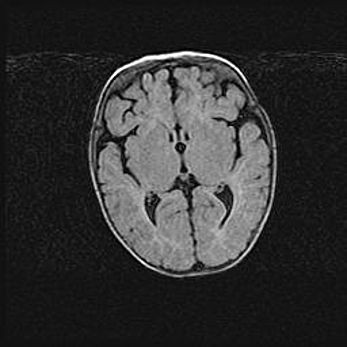

Неполная лизэнцефалия (пахигирия). Открытая гидроцефалия.

Возраст: 17 дней

Вес: 3110 г

Пол: мужской

Окружность головы: 33,5 см

Срок гестации: 35-36 недель

Лизэнцефалия—недоразвитие корковой пластинки и мозговых извилин в результате нарушения миграции нейронов коры. Поверхность мозговых полушарий гладкая. Микроскопически выявляется отсутствие нормальных слоев коры и скопление групп нейронов в подкорковом белом веществе.

Пахигирия—уменьшение числа вторичных извилин. В пораженном полушарии нервные клетки образуют толстый недифференцированный слой с неправильно расположенными нервными волокнами и группами гетеротопных клеток. Нервные клетки незрелые. Белое вещество истончено. При этом нередко аномально развит корково-спинномозговой путь.